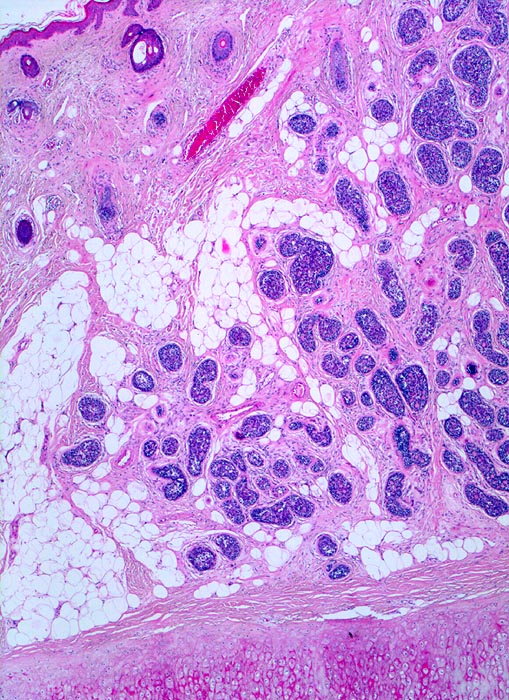

Adenoidzystisches Karzinom der Haut

Das zytologische Bild ist täuschend bland. Die Tumorzellen sind klein und monomorph, die Kern-Zytoplasmarelation ist hoch. Die Kerne sind dunkel, rund bis oval oder angulär und enthalten bisweilen einen kleinen Nukleolus. Typisch sind azelluläre Matrixkerne, um die die Tumorzellen angeordnet sind.